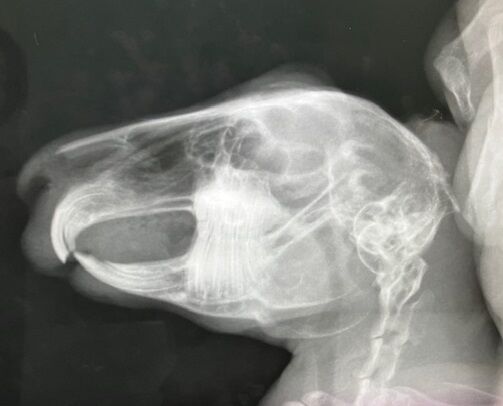

1月前半、まだ画像に納める余裕がある(^^;)